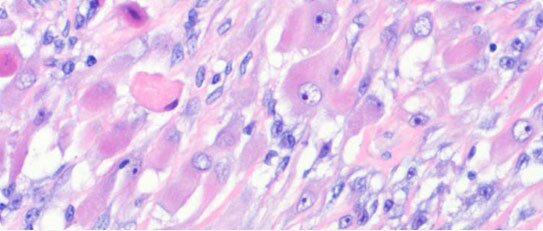

Sarcomas are malignant tumours that arise from cells that make up connective tissue (bone, cartilage, blood vessels, muscle, fatty tissue, nerves), and can develop at any site in the body. There are many different types of sarcoma, but it is useful to think of them as either soft tissue sarcomas or bone sarcomas. Sarcomas are rare cancers, and are only the 21st most common cancer. A GP can expect to see only one or two sarcomas in an entire career. There are approximately 2000 soft tissue sarcomas and 400 bone sarcomas diagnosed each year in the UK.